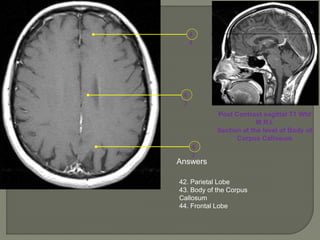

Post Contrast sagittal T1 Wtd

M.R.I.

Section at the level of Body of

Corpus Callosum

Answers

42. Parietal Lobe

43. Body of the Corpus

Callosum

44. Frontal Lobe